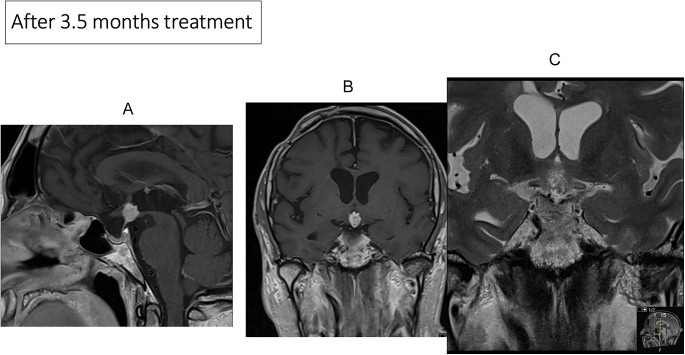

Summary: Craniopharyngiomas (CPs) are rare brain epithelial tumours arising in the suprasellar region, infiltrating adjacent areas causing visual loss, panhypopituitarism, cognitive deficits and morbid obesity. Papillary CPs (PCPs) harbour in 94% BRAF mutation cases. Two patients with PCP and BRAF V600E mutations but with different tumour status were treated with BRAF and MEK inhibitors. Case I was diagnosed with biopsy and treated for 16 months with BRAF and MEK inhibitors. After 3.5 months, there was a 50% reduction of the tumour volume, and after 13 months, the tumour volume decreased from 2220 to 90 mm3 (96%). Two months after stopping the drugs, he was treated with fractionated cranial irradiation (54 Gy). No recurrence of the PCP was recorded. Eight months after stopping the drugs, he was diagnosed with an adenocarcinoma of the oesophagus, which led to his death 12 months later. In case II, a woman had had four surgeries due to recurrences of a PCP, and a BRAF V600E mutation was confirmed. After a new recurrence measuring 14 × 12 × 18 mm, she was started on BRAF and MEK inhibitors. After 4 months of treatment, a significant decrease to 8 × 9 × 13 mm was recorded. The treatment continued for 31 months, and the MRI demonstrated a stable unchanged size including scar tissue, with a volume reduction from 633 to 483 mm3. During treatment, her visual acuity improved in her left eye from 0.05 to 0.3. After stopping the drugs, 'watchful waiting' with repeated MRI was decided. She is now off treatment for 25 months, without any recurrence on MRI.